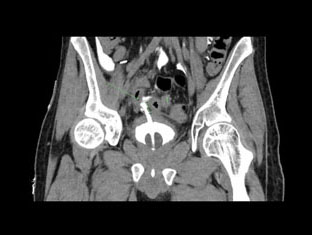

The patient is a 25-year-old man who sustained a T12 spinal cord injury July 2020 resulting in neurogenic bladder managed with self-exchanged IDC. He was previously noted at flexible cystoscopy to have a superficial false passage on the ventral surface of the penile-bulbar urethral junction. These were reported as healed at flexible cystoscopy in 2021. He first presented in April 2023 to a regional hospital complaining of a 36-hour history of decreased appetite, right iliac fossa pain, and subjective fevers. An ultrasound abdomen (Figure 1) demonstrated a small amount of free fluid in the right pelvis and a 7 mm blind ending tubular structure with surrounding hyperemia, echogenic fat, and local tenderness—felt to be in keeping with acute uncomplicated appendicitis. He subsequently proceeded to laparoscopic appendectomy and was found intraoperatively to have appendix and omentum adherent to his bladder, underneath which his IDC was seen to have eroded into the peritoneal cavity. The defect was laparoscopically repaired and patched with omentum, and an IDC reinserted. The bladder was noted to appear chronically inflamed [thickening of bladder wall noted on CT 2 months prior (Figure 2)]. He was managed post-operatively with intravenous (IV) antibiotics and discharged five days later. Computed tomography (CT) cystogram 10 days later showed no leak (Figure 3). He was discharged with an IDC at this time.

Figure 3: Image from CT cystogram 13th April 2023, demonstrating normal appearance of urinary bladder with no evidence of contrast leak.